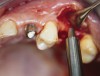

A full-thickness mucoperiosteal flap was raised, and alternating osteotomes were used to prepare the implant site. After achieving a length of 7 mm (Figure 7A and Figure 7B), heterologous bone graft was implanted and the osteotome sequence was repeated. The implant showed primary stability.

Figure 7A and Figure 7B Alternating osteotomes with variable conicity used to perform the alveolar remodeling in the area of tooth No. 15.

Figure 7a  Alternating osteotomes with variable conicity used to perform the alveolar remodeling in the area of tooth No. 15.

Figure 7a

Figure 7b  Alternating osteotomes with variable conicity used to perform the alveolar remodeling in the area of tooth No. 15.

Figure 7b